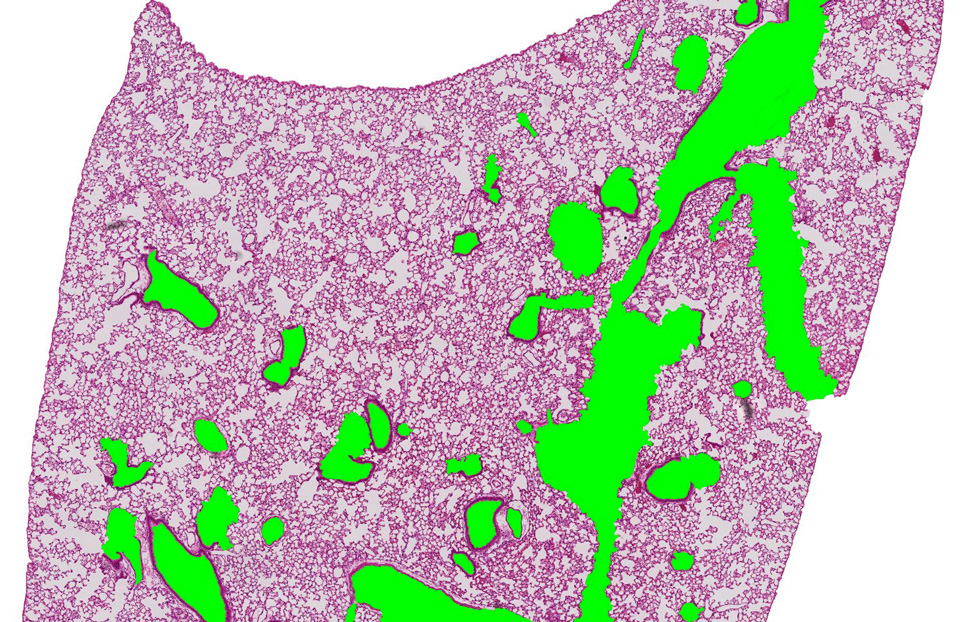

Parenchymal Airspace Profiling: Sensitive Quantification and Characterization of Lung Structure Evaluating Parenchymal Destruction. Xiao R, Goldklang MP, D’Armiento JM.

5. Tissue Fraction (TF) and Ductal/Destructive to Alveolar Ratio (D2A = DF/AF) have been added to the data report. TF is particularly helpful to detect scarring tissue and changes in alveolar wall thickness. Since various reasons, including those mentioned above and thickness of each section, can affect tissue fraction, D2A (Ductal/Destructive to Alveolar Ratio, DF/AF) was introduced to make comparisons only between different categories of airspaces, other than the tissue. The D2A parameter has been tested and found to be more sensitive and robust in detecting mild emphysema, compared to DF.